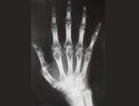

5.X线检查:早期患者的关节X线检查除软组织肿胀和关节腔渗液外一般都是阴性。关节部位骨质疏松可以在起病几周内即很明显。关节间隙减少和骨质的侵蚀,提示关节软骨的消失,只出现在病程持续数月以上者。半脱位,脱位和骨性强直后更后期的现象。当软骨已损毁,可见两骨间的关节面融合,丧失原来关节的迹象。弥漫性骨质疏松在慢性病变中常见,并因激素治疗而加重。无菌性坏死的发生率特别在股骨头,亦可因用皮质类固醇治疗而增多。

最早受累的为腕、掌指关节(MCP)和近端指间关节(PIP)。腕背肿胀(伸肌腱鞘内)是最早的症状之一。大关节的症状常在小关节症状明显后才出现,但也有人认为是因为大关节症状在早期不明显所致。有统计表明:发病早期有58%~65%的病人有掌指关节(MCP)受累,有57%~60%的病人有腕部受累,有53%~63%的病人有近端指间关节(PIP)受累。在疾病后期,87%的患者的掌指关节受累,近端指间关节受累者为63%,腕部关节受累者为82%。所以,如果出现近端指间关节梭形肿胀、腕背肿胀,特别是肿胀对称时要作进一步检查。